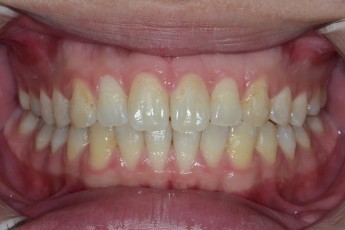

BEFORE & AFTER

- 돌출입교정